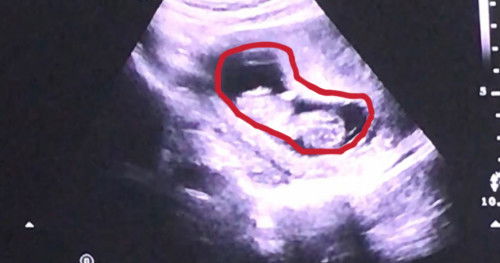

hasil usg 11 week , bun mau tanya ..

bun mau tanya, skrg khamilan aku minggu ke 12 , kok kantungnya kayanya kcl ya bun? si ruang bayi nya ituloh , apakah gpp bun? normal kah? yang difoto ini kmrin pas usg week 11 , aman si bun klo kata dokter .. trs aku lupa tanya , soal ini ke dokterny .. mungkin bunda2 ad yg paham? aku aga tkut bayiny ksempitan didlm krna krg ketuban atau apa gt..🙏🏻 terima kasih sebelumny..